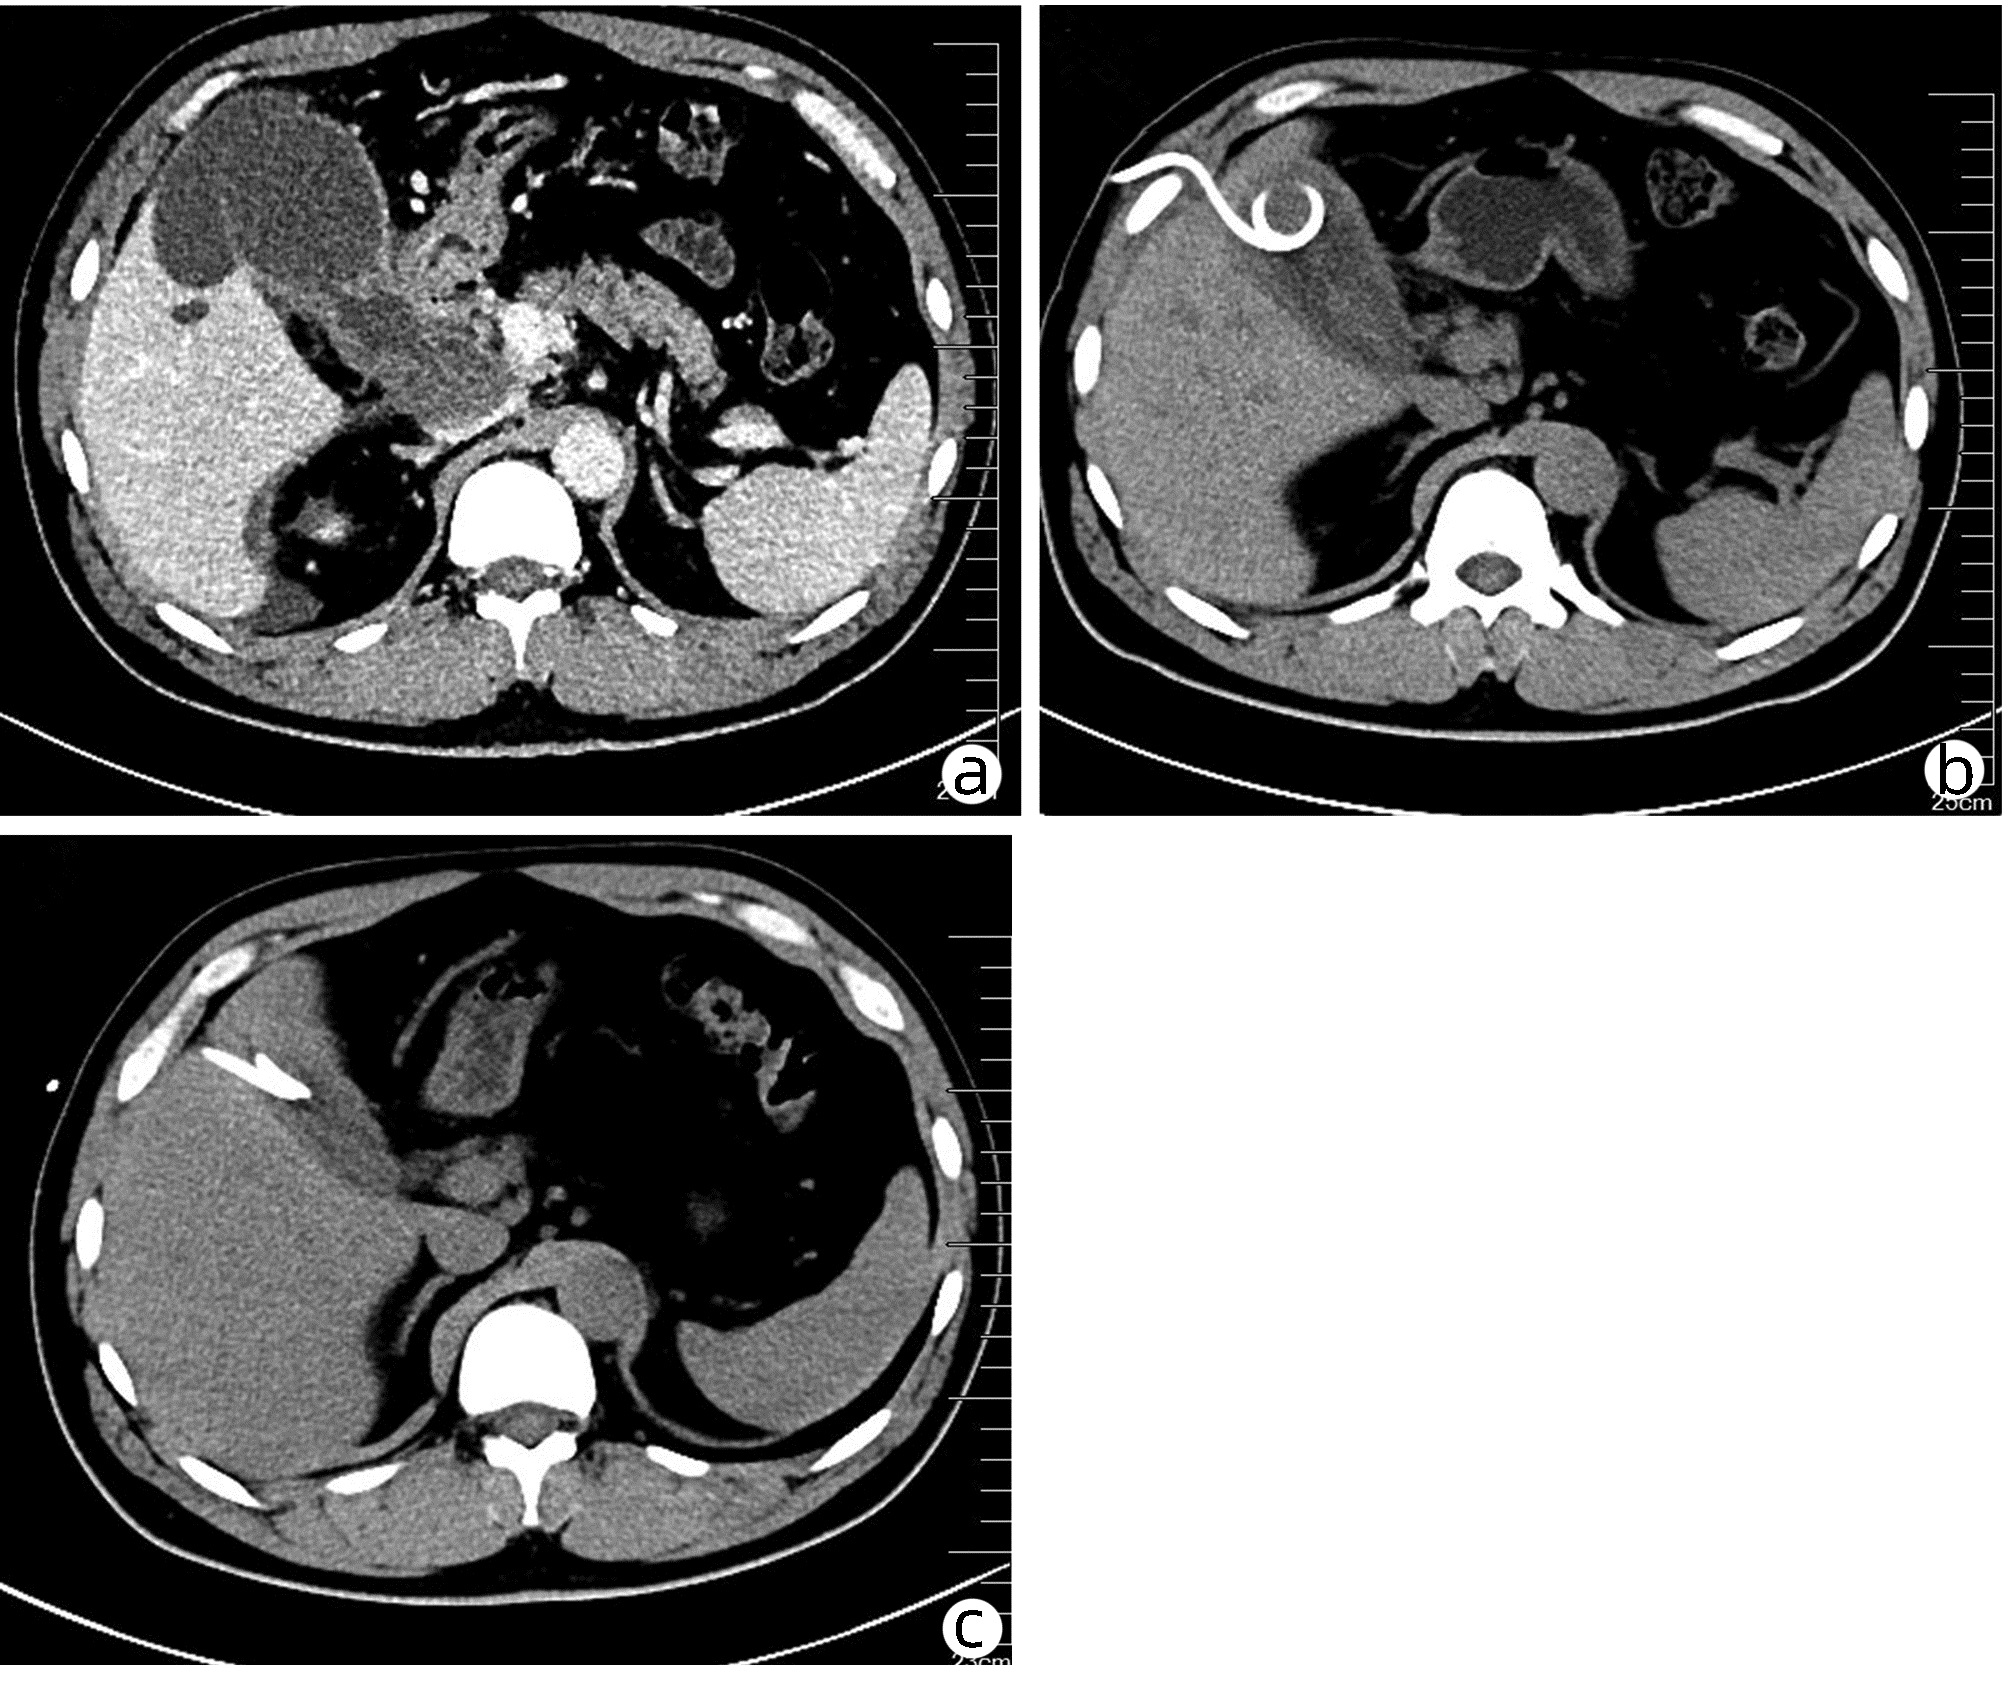

A case of spontaneous hepatic rupture and hemorrhage after liver transplantation

Jian MA, Lihong HE, Lingyun WANG, Yanan ZHAI, Xun LI, Lei ZHANG

2022, 38(4): 891-893. DOI: 10.3969/j.issn.1001-5256.2022.04.030

Abstract(1075) HTML (365) PDF (3041KB)(60)

Abstract: